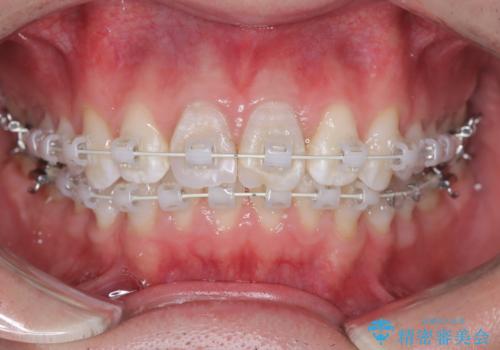

【ワイヤー矯正 11ヵ月で矯正終了!】歯のでこぼこを治したい!

- 「歯のでこぼこを治したい 1年くらいで矯正を終わらせたい」を主訴に来院された患者様です。

叢生量は多く無く歯の傾斜も標準傾斜だったので歯は抜かずにワイヤー矯正で治療を行いました。

左側は2級傾向が強く臼歯の遠心移動をご提案しましたが、1年以内に矯正を終わらせたいという患者様のご意向で希望されず叢生を改善する矯正となりました。